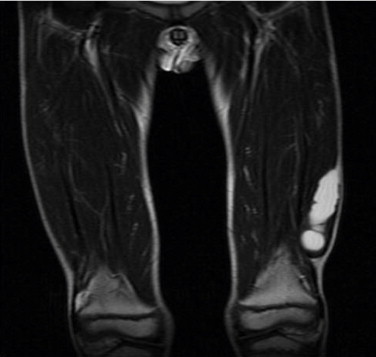

Firstly, ultrasound examination was performed and it showed multiple cystic lesion in the muscle localized on vastus lateralis. Magnetic resonance imaging (MRI) was performed for further imaging. MRI showed oval cystic mass approximately 77 × 20 × 18 mm in the left vastus lateralis muscle, containing round-shaped daughter cysts (Fig. 2). The cysts seen hypointense in T1 A weighted images and hyperintense in T2 A weighted images (Fig. 3).

Fig. 2.

Frontal view of MRI with T2 weighted images showing cystic mass in the left vastus lateralis muscle. The enlargement of the mass is approximately 77 × 20 × 18 mm.